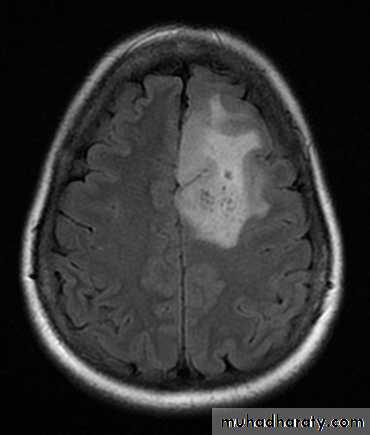

These are the most common primary tumors they arise form the glial cells which are part of the supportive tissue of the brain

There are many types of glioma with different degrees of malignancy:

Astrocytomas:have 4 grades I -> IV. These are the most common gliomas, there are 4 grade of astrocytoma depending on the degree of malignancy, it can affect any age , usually yellow - whitish in color affecting both cerebrum and cerebellum , it can affect ages from 2 months ~ 95 years.

arise from the epidermal lining of the ventricular system, usually whitish in color & can lead to early hydrocephalusCT scan of all gliomas shows usually hyperdense lesion, irregular in shape, surrounded by edema & may be enhanced with or without cystic degeneration.

Note: all gliomas are dealt with by surgical intervention ,by excision of the tumor followed by radiotherapy , but prognosis is not very good & fluctuates from 5 years survival of less than 5% in Glioblastoma multiformis to up to 100% 5 years survival in Oligodendroglioma treated by surgery & successive radiotherapy.